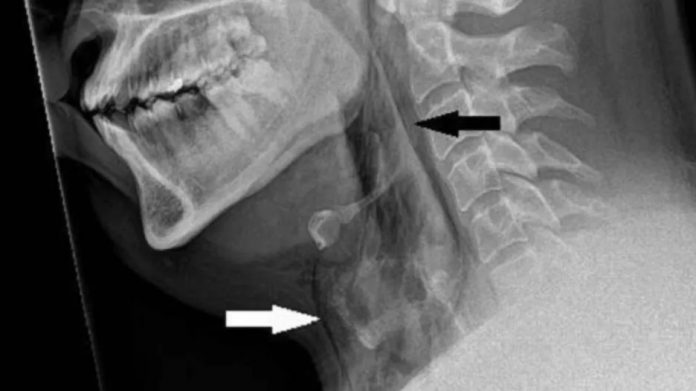

El accidente ocurrió cuando el hombre, con antecedentes de rinitis alérgica, conducía su automóvil con el cinturón de seguridad puesto. De inmediato su cuello se inflamó, y una radiografía reveló su padecimiento.

La herida en la tráquea del paciente tiene dimensiones de 2 milímetros x 2 mm x 5mm, y se encuentra entre la tercera y cuarta vértebra.